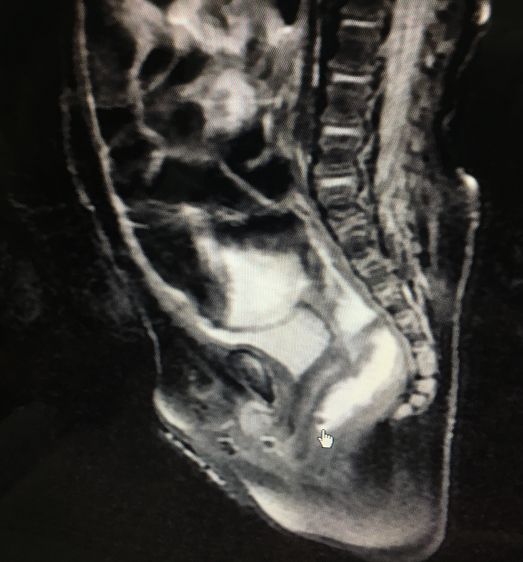

今年3月17日(上周五),马达主任刚做了一个女婴无肛门的手术,她5个月大,虽然没有肛门,但有一个畸形的瘘孔可以排便,而且和阴道共用出口。手术除了重建肛门,还要把这个瘘孔堵上。手术很顺利。

(这名女婴的拍片)